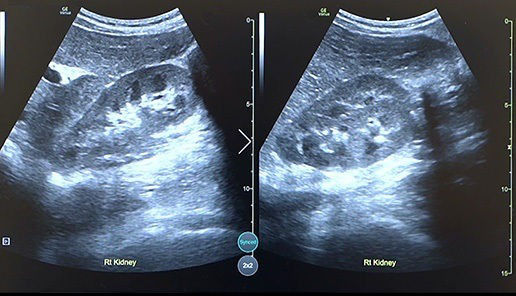

Quickly assess kidneys and the bladder with Renal Diagram

Simplify documentation and provide easy follow up for patients with suspected hydronephrosis. No need to type findings; simply assign a label from a pre-populated list that correlates with images.